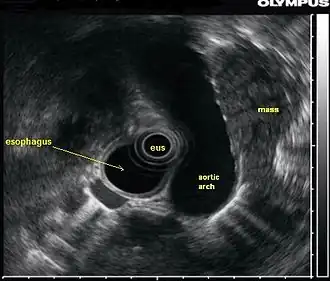

![]() In this endoscopic ultrasound image, a mass (in this case, from lung cancer) is visualized using an ultrasound probe (EUS) inserted into the esophagus. | |

An endoscopic ultrasound probe placed in the esophagus can also be used to visualize lymph nodes in the chest surrounding the airways (bronchi), which is important for the staging of lung cancer. Ultrasound can also be performed with an endoscopic probe inside the bronchi themselves, a technique known as endobronchial ultrasound.